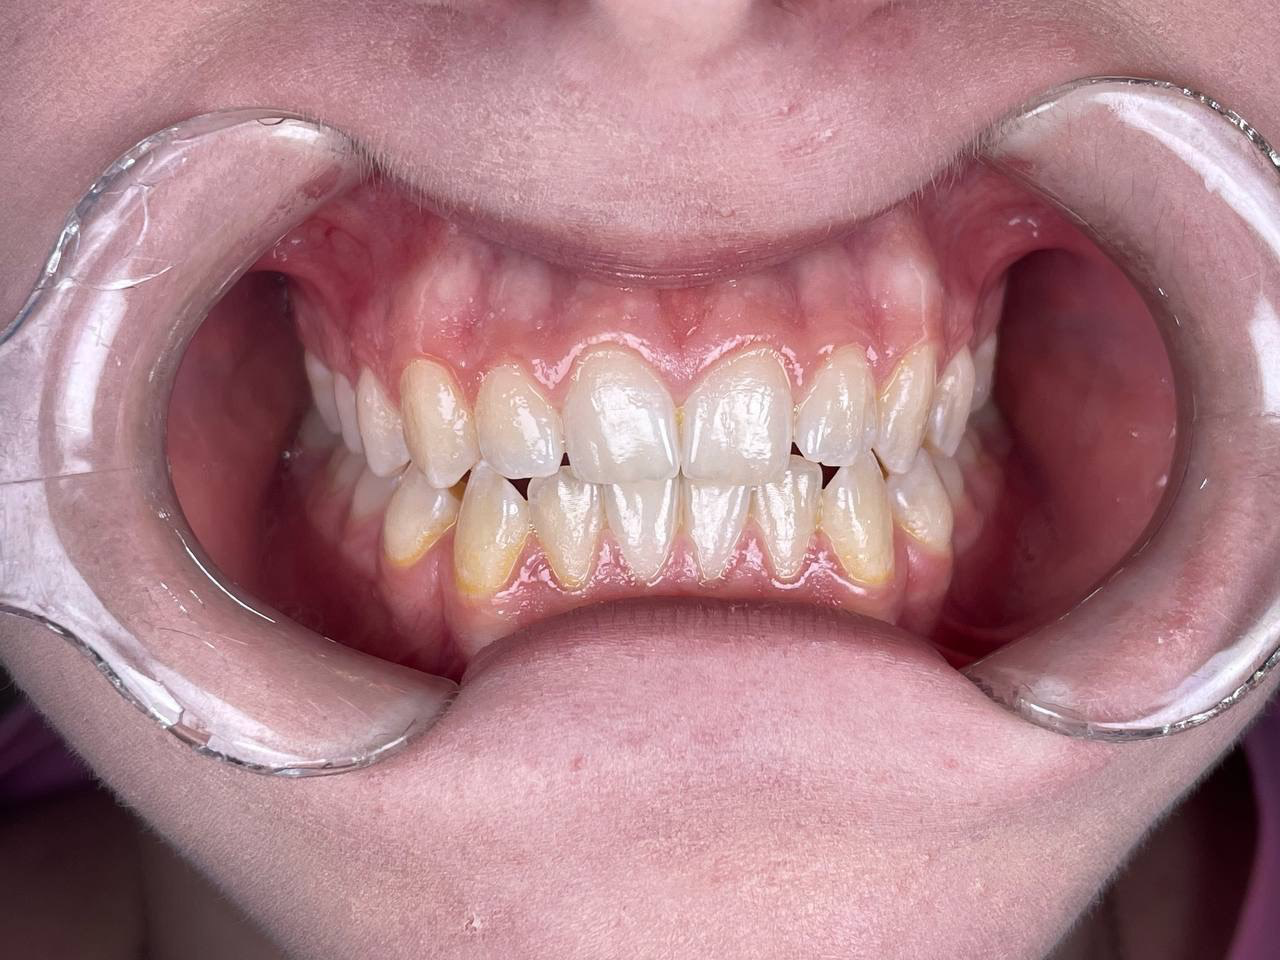

Кейін

Кейін

Кейін

Кейін